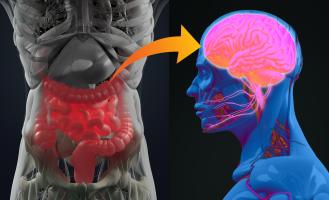

PARKINSON : La maladie pourrait commencer dans l’intestin

PARKINSON et MICROBIOTE : Quand l'alpha-synucléine voyage du cerveau à l'intestin